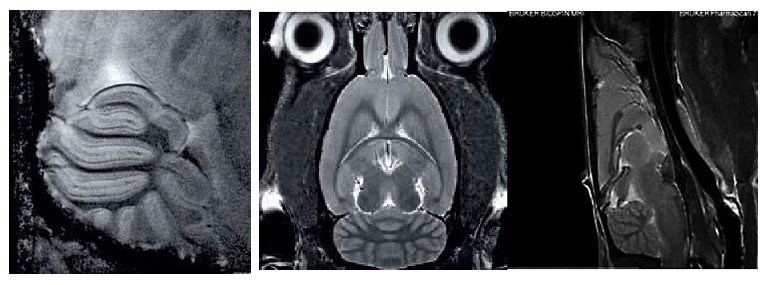

1、高分辨率神經(jīng)解剖結(jié)構(gòu)

布魯克結(jié)合超高磁場(chǎng),先進(jìn)的相陣控線圈和譜儀技術(shù)提供完美品質(zhì)的結(jié)構(gòu)形態(tài)成像。超高空間分辨率可以顯示精細(xì)的顯微組織結(jié)構(gòu)。領(lǐng)先的磁共振成像技術(shù)在超高磁場(chǎng)下提供完美的對(duì)比度。

磁共振成像低溫探頭增加150%的靈敏度,清晰顯示小鼠腦部細(xì)胞層狀結(jié)構(gòu)(小腦的顆粒層和浦肯雅細(xì)胞層),空間分辨率達(dá)到 50μm:

2、功能磁共振成像

3、擴(kuò)散張量成像DTI

多次激發(fā)EPI擴(kuò)散張量成像可以顯示小鼠腦部神經(jīng)纖維走向。擴(kuò)散梯度方向可多達(dá)256個(gè)方向,空間分辨率為200×200×400微米。

小鼠腦部擴(kuò)散張量成像:

4、SWI磁敏感成像

磁敏感成像可大大提高磁敏感性,可用于檢測(cè)老年癡呆小鼠模型粥狀淀粉沉積斑塊,評(píng)價(jià)藥物作用療效。

老年癡呆小鼠腦部的磁敏感成像:

9、猴腦成像

靈長(zhǎng)類動(dòng)物是我國(guó)腦科學(xué)計(jì)劃中關(guān)鍵實(shí)驗(yàn)動(dòng)物,對(duì)理解大腦的功能運(yùn)轉(zhuǎn)有極大的作用。可以實(shí)現(xiàn)小型絨猴靈長(zhǎng)類動(dòng)物成像,大大提高空間分辨率。

絨猴的大腦成像: